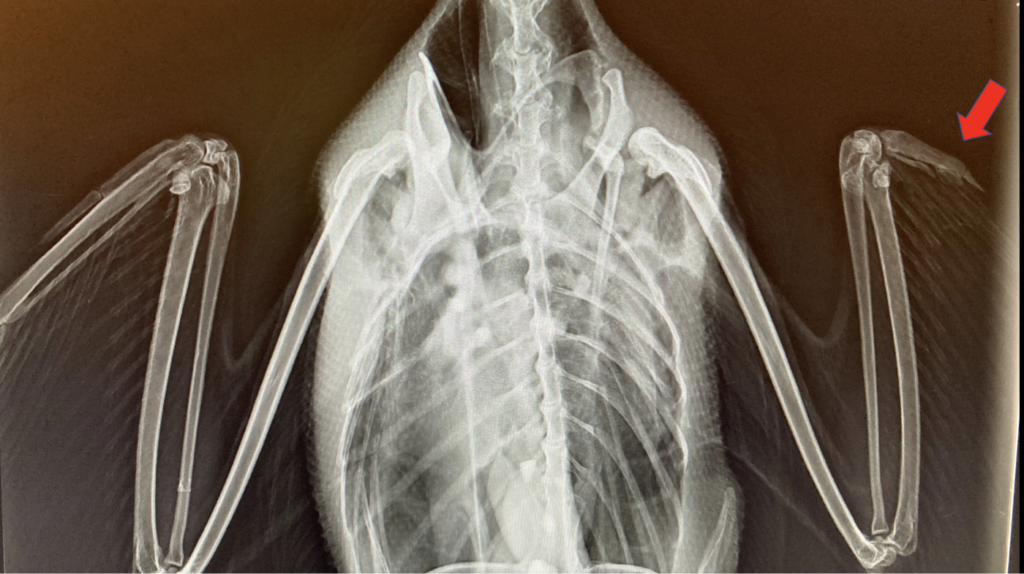

Photo by Wild & Free wildlife rehabilitation center showing an x-ray of a common loon with an injured wing, likely caused by a boat propellor.